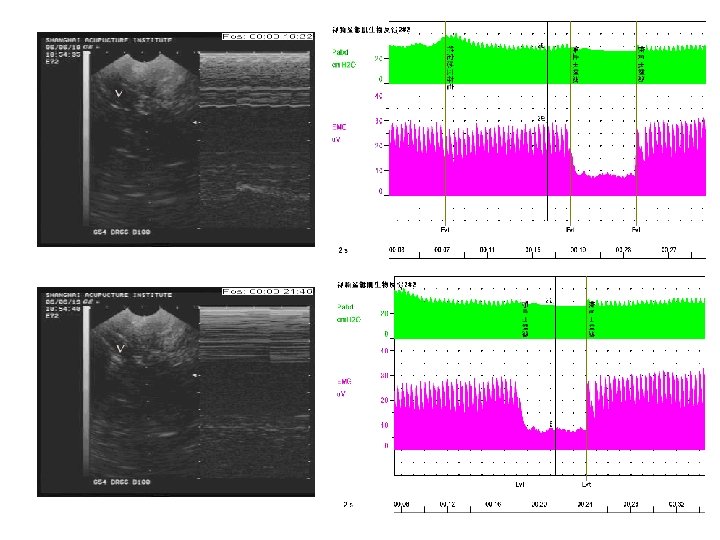

• Electrical pudendal nerve stimulation • After the needling sensation referred to the above regions was produced, a G 6805 -2 Multi-Purpose Health Device was connected with the inserted needles used as electrodes. The device was set to produce an electrical stimulation at a frequency of 2. 5 Hz (150 times/min) and an intensity as high as the patient could tolerate without discomfort. The electroacupuncture was set for 60 minutes each time. • 3. 电针阴部神经刺激疗法 • 针感达特定部位后接G 6805Ⅱ治疗仪。电针采 用连续波,频率约 2. 5 Hz (150次/分),强刺激 以患者不感到难受为度,每次持续 60分钟。

• Electrical pudendal nerve stimulation • Strong rhythmic and cephalad contraction of the pelvic floor muscles around the urethra must be kept during the electroacupuncture. • The treatment was given once every other day. The treatment course was based on the patient’s condition. • 电针期间需保持盆底肌以尿道为中心有节律地 向上(头部方向)强烈收缩的感觉。 • 治疗隔日 1次,治疗次数视病情而定。